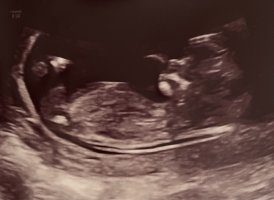

På grunn av vinkelen på rumpa så er jeg litt usikker her om jeg får vinkelen riktig, men det ser jentete ut. Hvis du deler den på nubqueens på facebook så kan de svare med større sikkerhet på denne tror jegVis vedlegget 417058